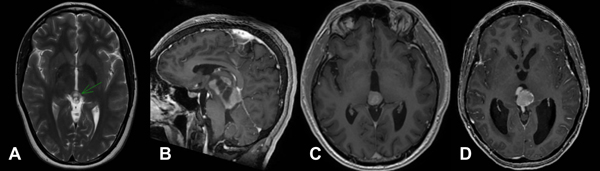

Figura 1. RM de lesiones pineales

Referencias: A. T2, quiste pineal tabicado B. T1 con contraste, Tumor germinal. C. T1 con contraste,

Tumor papilar de región pineal. D. T1 con contraste, Tumor pineal de diferenciación intermedia.